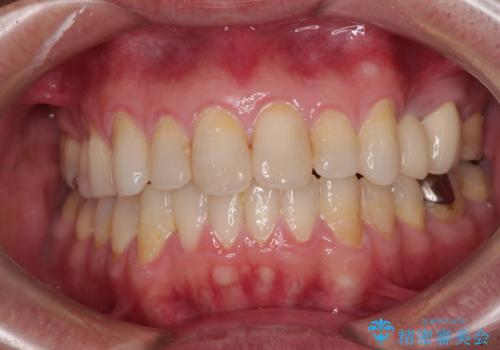

[ 金属アレルギー ] 銀歯を除去するメタルフリー治療

担当医 大元洋佑